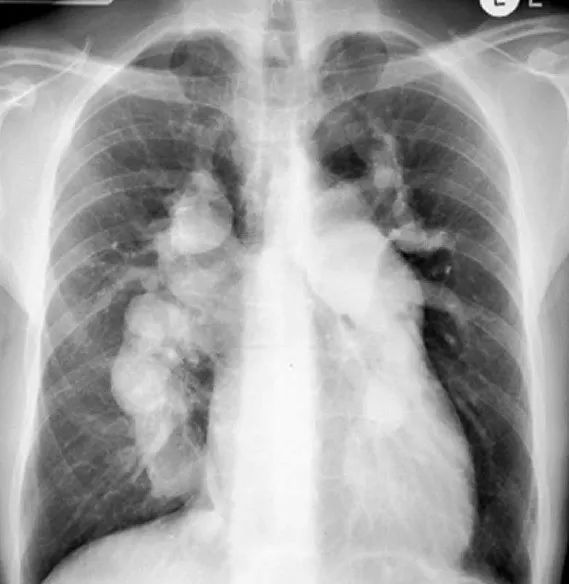

CTEPH的病因:為何血栓會引發(fā)肺動脈高壓?1.初始誘因:肺動脈血栓栓塞急性肺栓塞未完全溶解部分患者發(fā)生急性肺栓塞后,血栓未被身體完全溶解或吸收,殘留的血栓堵塞肺動脈分支(如圖1黑色箭頭所指)。??正常情況:人體通過纖溶系統(tǒng)逐漸溶解血栓,血管再通。??CTEPH情況:血栓機化(變硬)、黏附在血管壁上,形成“瘢痕樣”阻塞。2.血管重塑:肺動脈高壓的關(guān)鍵機制殘留血栓會觸發(fā)血管壁的異常修復反應,導致:血管狹窄:血栓機化后壓迫血管腔。小血管病變:下游未堵塞的小肺動脈因血流減少而收縮、內(nèi)膜增厚(如圖2)。血流阻力增加↑:肺動脈網(wǎng)絡變窄或堵塞,右心室需更用力泵血,最終導致肺動脈壓力升高。3.危險因素以下情況更易發(fā)展為CTEPH:反復肺栓塞病史凝血功能異常(如抗磷脂抗體綜合征)脾臟切除術(shù)后慢性炎癥性疾病不明原因的肺栓塞發(fā)病時間至診斷時間超過2周的肺栓塞

簡單來說,就是肺動脈(連接心臟和肺的血管)里長期有血塊堵住,這些血塊像凍豆腐一樣,導致血管變窄、血流不暢,心臟需要更用力泵血,時間久了心臟負擔加重,可能引發(fā)心衰。為什么會得這個病?主要原因:以前得過肺栓塞(肺部血管被血塊堵住),但血塊沒有完全溶解,慢慢變成“疤痕”一樣的東西,長期堵住血管。其他風險:有反復腿血栓(深靜脈血栓)病史;血液容易凝固(比如某些遺傳病或免疫疾?。?;做過脾臟切除手術(shù)等。有哪些癥狀?早期可能只是“容易累、氣短”,但隨著病情加重,會出現(xiàn):稍微活動就喘不過氣(比如爬樓梯、走路比原來費勁);胸口悶或疼(心臟負擔大);腿腫、肚子脹(因為心臟功能變差,血液回流不暢);突然暈倒(嚴重時心臟供血不足)。??注意:很多患者誤以為是“體質(zhì)變差”或“年紀大了”,耽誤就診!如果曾經(jīng)得過肺栓塞或腿血栓,之后長期氣短,一定要檢查。如何確診?CT肺動脈造影(CTPA):像拍片子一樣,看肺動脈有沒有堵塞。肺灌注掃描(V/Q掃描):非常重要又容易被忽視的檢查,可檢查肺部血流是否正常,尤其是外周小血管的病變。心臟超聲:初步估測心臟壓力和功能,是簡單有效無創(chuàng)的篩選方法。右心導管檢查(確診金標準):醫(yī)生會從脖子或大腿插一根細管到心臟,直接測肺動脈壓力。肺動脈造影:配合右心導管檢查,通過造影圖像,共同明確慢性血栓栓塞性肺動脈高壓診斷。怎么治療?1.手術(shù)——肺動脈內(nèi)膜剝脫術(shù)(PEA)適合誰?血栓主要在大的肺動脈,且身體能承受手術(shù),因該手術(shù)需要在亞低溫心臟停跳情況下完成,手術(shù)難度大。效果:多數(shù)人術(shù)后癥狀明顯改善,甚至可能治愈。風險:手術(shù)較大,需要在有經(jīng)驗的醫(yī)院做。2.微創(chuàng)治療——肺動脈球囊成形術(shù)(BPA)用小球囊撐開狹窄的肺動脈,適合遠端小血管堵塞或不能手術(shù)及不愿行PEA手術(shù)的患者。部分患者經(jīng)過多次肺動脈球囊成形術(shù)治療后,其肺動脈高壓甚至可以回落至正常范圍,達到類似PEA手術(shù)的效果。3.藥物抗凝藥:如華法林、利伐沙班,防止新血栓形成(需長期甚至終身服用)。降肺動脈壓藥:如利奧西呱,幫助擴張血管、減輕心臟負擔(適合不能手術(shù)或術(shù)后仍有高壓的患者)。